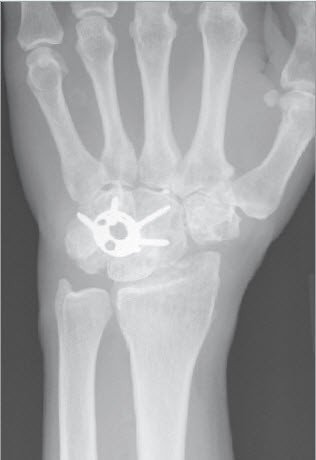

Eine Verdachtsdiagnose kann bereits durch die Patientenbefragung und das aktuelle Beschwerdebild gestellt werden. Gesichert wird die Diagnose einer Arthrose dann durch ein Röntgenbild. Findet sich nur eine leichte Arthrose, müssen möglicherweise Zusatzuntersuchungen durchgeführt werden. Bei fortgeschrittenen Arthrosen mit Gelenkzerstörung findet sich im Röntgenbild nur noch ein schmaler oder auch gänzlich fehlender Gelenkspalt (Abb. 1a bis 1c).

Die Medizin versteht unter Arthroplastiken einen Vorgang, bei dem eine zerstörte Gelenkfläche entfernt und Weichteilgewebe eingeschoben oder mit einem Kunstgelenk oder einer Gelenkprothese ersetzt wird. Am Handgelenk sind grundsätzlich beide Verfahren möglich. Der Vorteil einer biologischen Arthroplastik ohne Verwendung eines künstlichen Implantats besteht darin, dass es zu keinen Komplikationen wie der Lockerung der implantierten Prothesenkomponenten kommen kann.

Die Proximale Row Carpektomie (PRC) stellt eine Sonderform der biologischen Handgelenk-Arthroplastik dar, indem die gesamten Knochen der ersten Handwurzelreihe entfernt werden. Durch die günstige Form des grössten Knochens der zweiten Handwurzelreihe (Kopfbein) entsteht eine gute Korrespondenz mit der Speiche. Aus einem zweireihigen Gelenk wird so ein einreihiges.

Diese Form der Arthroplastik kommt ausschliesslich nach Unfällen mit Teilzerstörung des Handgelenkes und bei der Durchblutungsstörung des Mondbeines (Lunatummalazie) in Betracht. Voraussetzung ist, dass die Gelenkflächen der Speiche und des Kopfbeines nicht zerstört sind. Nach einer Operation ist eine kurze äussere Ruhigstellung während drei bis vier Wochen erforderlich, wobei das Gelenk aus der Schiene heraus unter ergotherapeutischer Anleitung bereits eingesetzt werden kann.